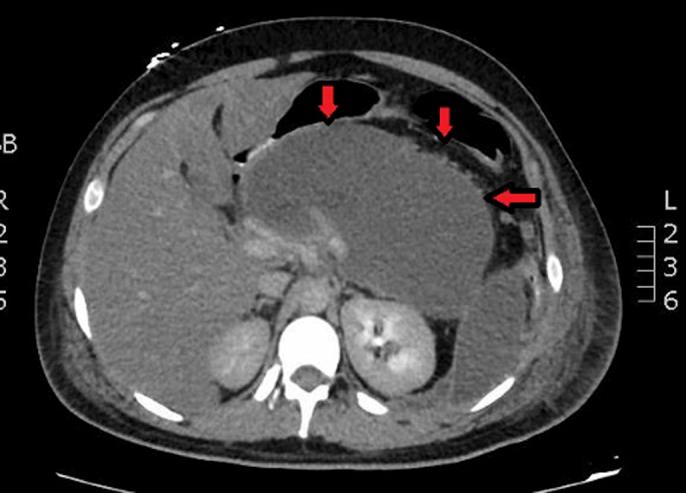

Propofol is a widely used sedative for gastrointestinal endoscopic procedures. Drug-induced pancreatitis is a relatively rare disease possibly because of poor recognition. Propofol-induced pancreatitis is an extremely rare phenomenon. We present a 22-year-old healthy man who underwent esophagogastroduodenoscopy with propofol as a sedative. Soon after, he developed acute upper gastrointestinal symptoms and was diagnosed with pancreatitis. His prolonged hospital course was complicated with necrotizing pancreatitis, acute respiratory distress syndrome, septic shock, and other end-organ damages. We hope to increase awareness of a life-threatening adverse event of a commonly used anesthetic such as propofol.

丙泊酚是一种广泛用于胃肠内镜检查的镇静剂。药物性胰腺炎是一种相对罕见的疾病,可能是因为认识不足。丙泊酚诱导的胰腺炎是一种极其罕见的现象。我们报告一名22岁的健康男性,他在丙泊酚镇静下接受了食管胃十二指肠镜检查。此后不久,他出现了急性上消化道症状,并被诊断为胰腺炎。他的住院病程延长,并发坏死性胰腺炎、急性呼吸窘迫综合征、感染性休克和其他终末器官损害。我们希望提高对丙泊酚这种常用麻醉剂危及生命的不良事件的认识。